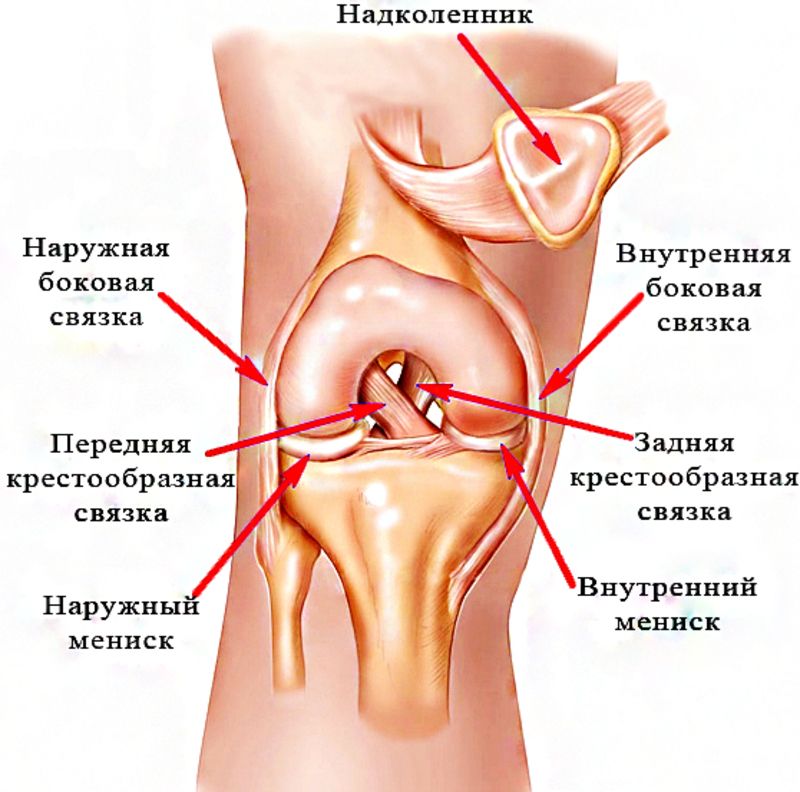

Проблемы с коленным суставом: флоттация и лечение